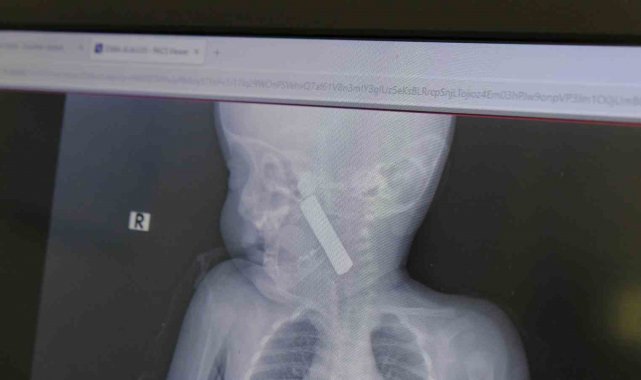

Yaşanan olayla ilgili bilgi veren Doç. Dr. Mehmet Uysal, "Acil polikliniğimize kusma şikayeti ile 6 aylık bir kız bebek getirilmiş ve bize haber verildi. Biz de vakit kaybetmeden geldik, hastamızı gördük. Yapılan tetkikler sonucunda, ağız tabanına oturan ve yemek borusunun birinci darlığına kadar uzanan, kumanda pili dediğimiz bir pille karşılaştık. Filmde ve muayenede bunu gördük. Hastayı ilk gördüğümüzde bayağı siyanotik durumda, solunum sıkıntılıydı ve oksijen satürasyonu 90 civarındaydı. Böyle olunca bir an önce beklemeden hızlı bir şekilde ameliyathaneye götürdük. Orada ameliyathanedeki anestezi uzmanlarımız ve personel bize yardımcı oldu, hasta hızlı bir şekilde entübe edildi. Ondan sonra da laringoskop ve magill forseps dediğimiz malzemelerimizle bu yabancı cismi çıkarmış olduk. Bir an evvel müdahale ettik, iyi ki müdahale ettik, orada ağız tabanında, özellikle ön kısmında hasar oluşmuştu. Müdahale sonrasında da hastanın solunum problemleri bir süre devam etti, bu yüzden 24 saat takip ettik. Herhangi bir problem oluşmayınca 24 saat sonra kontrole gelmek üzere hastayı taburcu ettik" diye konuştu.